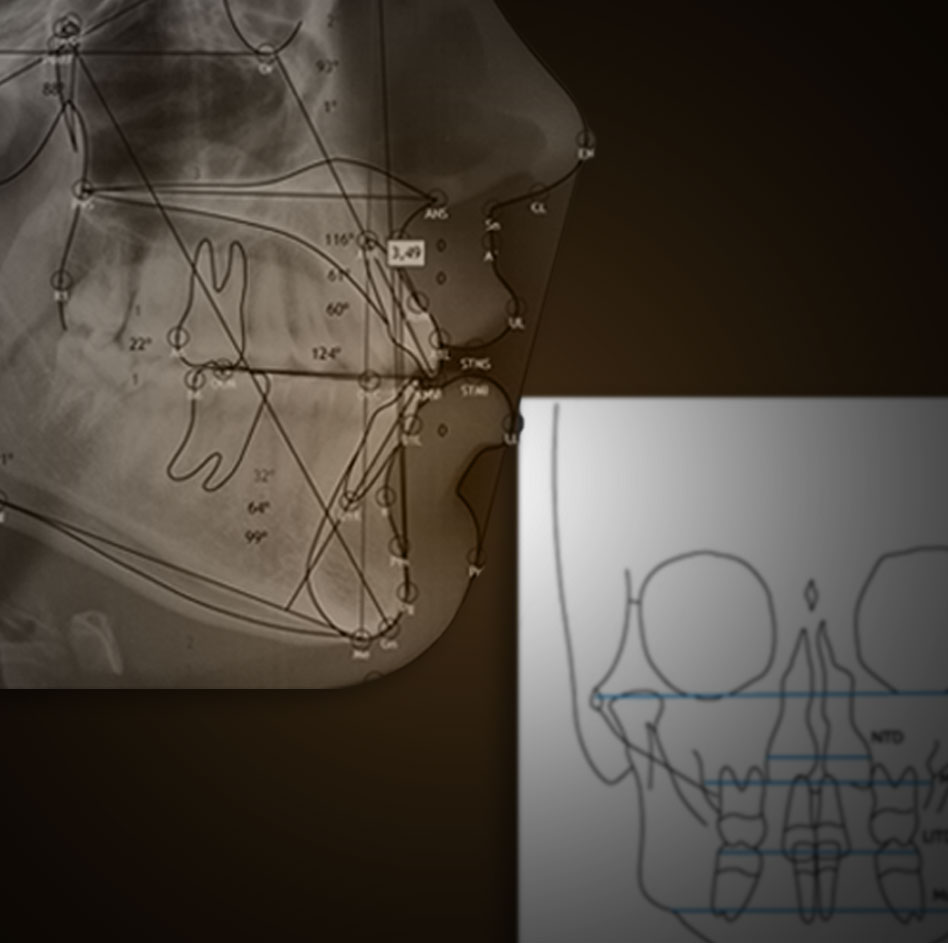

Estructuras anatómicas 100% configurables. Introducción de estructuras libres y puntos de control. Importación y exportación tanto de configuraciones de estudios cefalométricos, como de los propios estudios. Exportación de tablas y datos a excel.

Ricketts, Ricketts frontal, Steiner, McNamara, Jarabak, tejidos blandos, y otros. Predicción de crecimiento, STO y VTO. Superposición de estudios cefalométricos, imágenes o ambos.